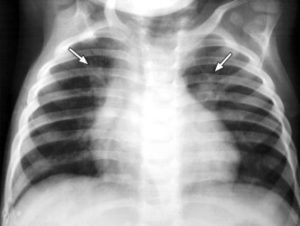

- Рентген грудной клетки (это стандартное исследование легких при подозрении на пневмонию, только так можно четко определить границы воспалительного поражения сегмента и туберкулезные затемнения).

Диагностика сегментарной пневмонии обычно включает физикальное обследование, рентгенографию грудной клетки и, при необходимости, компьютерную томографию. Также могут быть назначены лабораторные анализы, такие как общий анализ крови и анализ мокроты.